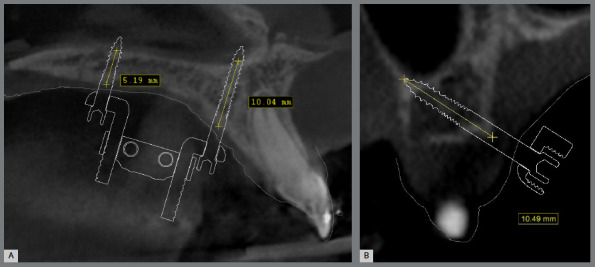

Objective: This cross-sectional study evaluated the bone thickness on mini-implants insertion site, the factors that influence the digital planning of MARPE appliance (miniscrew-assisted rapid palatal expansion), and its different designs.

Methods: A total of 135 plannings were assessed regarding the size of the expander screw used, the positioning and the type of the mini-implant rings, and their location in relation to the teeth. Bone thickness measurements were assessed in the region of the mini-implants' trajectory. Differences between the sexes was verified using the ANOVA test (5% significance).

Results: 73 cases were planned with 4 mini-implants and 62 cases, with 6 mini-implants. In 90% of cases, teeth #16 and #26 were used as supports, and the most used expander screw was 13mm (64.1% of cases). The anterior mini-implants of conventional MARPE showed more pronounced insertion in bone in males (5.9 ± 2mm; p= 0.025). The extra mini-implants (anterior region) were inserted with greater bone thickness in males (11.1 ± 2.3mm) compared to females (9.9 ± 1.8mm; p=0.041). A greater bone thickness was observed in males (10.1 ± 2.1 mm) when using mini-implants in the paramedian region.

Conclusion: Additional rings allow more pronounced bone insertion. Male patients had greater bone thickness, which may be related to greater difficulty in opening the sutures. The alveolar process region seems to be a satisfactory site for mini-implants to those patients with reduced bone thickness in the paramedian posterior region. MARPE appliance must be customized for each patient, due to bone thickness and anatomical variations.